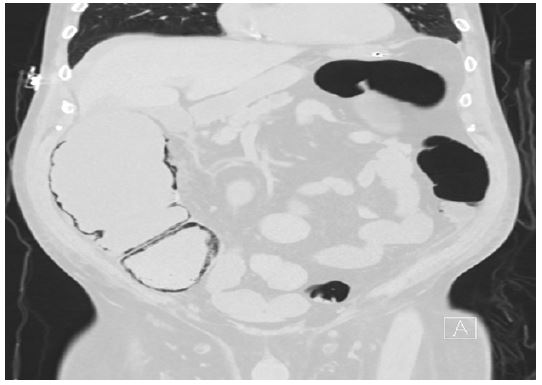

Hospital course

Figure 1: Abdominal x-ray film.